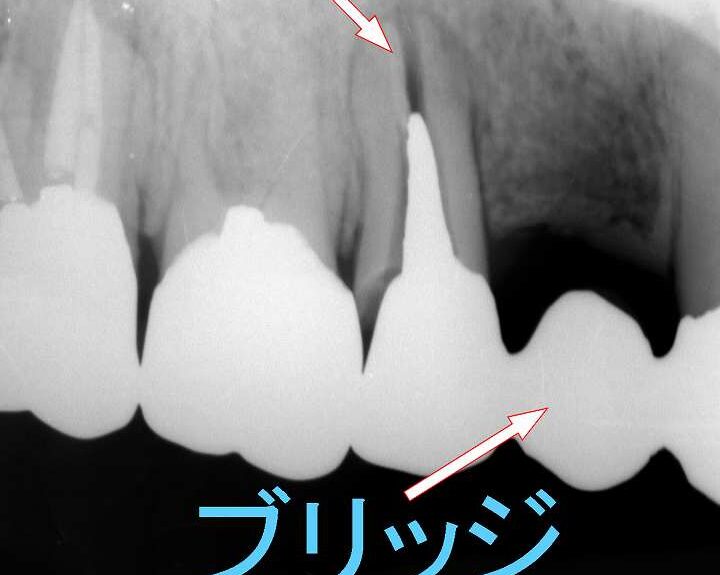

X線撮影

X線撮影は、最も一般的で広く使用される画像診断法です。この方法によって、歯や周囲の骨構造を詳細に評価することができます。X線写真には以下のような特徴があります:

- 迅速性: 検査自体が短時間で終了し、即座に結果を得られます。

- コスト効率: 他の高度な検査方法と比べて費用が低いため、多くの患者さんに利用されています。

- 初期評価: 亀裂や骨吸収などの問題を早期に発見できるため、その後の治療プランにも反映されます。

- クラウンやブリッジ: 歯根破折後に残存している部分に対してクラウンやブリッジでサポートします。